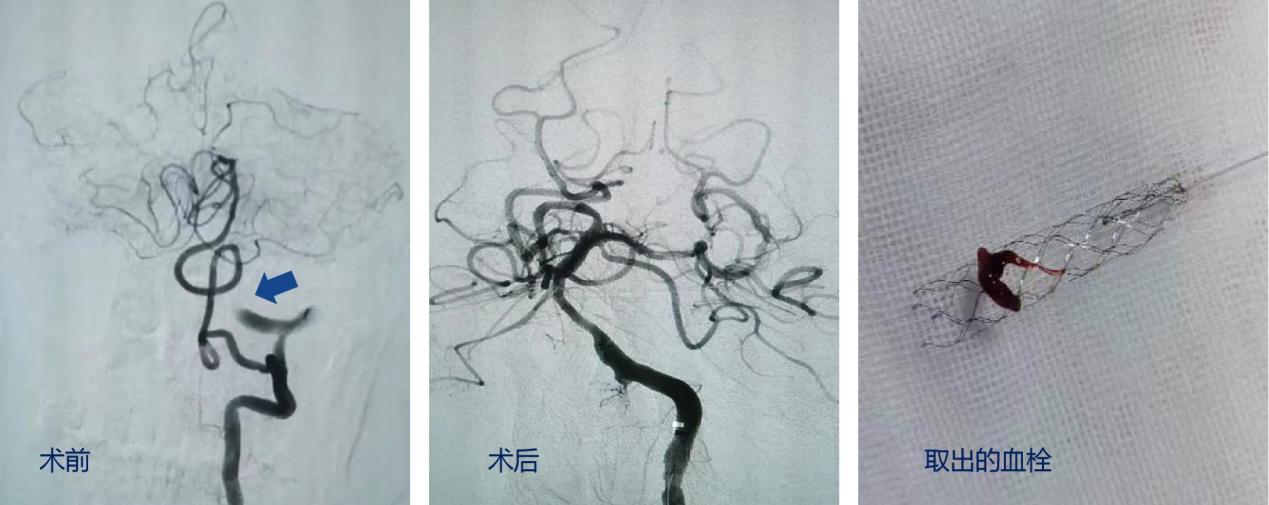

患者老年男性,10小时前突发意识障碍、左侧肢体瘫痪。随着患者到院,脑卒中绿色通道也立即启动。在影像科配合下,立即完善颅脑多模态影像学评估,诊断为脑干梗死、基底动脉闭塞。这个诊断让所有人的心都提到了嗓子眼,脑干是生命中枢,基底动脉闭塞预后极差,九死一生。面对如此凶险的病情,神经内科介入团队迎难而上,医生王虎清、李雯娴、樊洪、范松华、护士张倩、郑佳、杨金凤立即与家属沟通、进行术前准备。麻醉科迅速响应,医生李蓉飞快赶来。征得家属知情同意后,在全麻下行脑血管造影+基底动脉取栓术,血栓被顺利取出,基底动脉血流恢复,术后未苏醒患者。刘媛媛副护士长全力协调呼吸机,面对全院监护室满员、呼吸机紧张的现实情况,科室应机立断,手术室变监护室,麻醉医生协助麻醉机变呼吸机,医生护士兼顾病房工作的同时轮班对该患者进行特级护理。经过一通夜的接续奋战,患者逐渐清醒,瘫痪肢体也逐渐有了些许力量,转回普通病房。经过一周的规范治疗,患者目前已康复出院。出院时意识清醒,言语稍含糊,四肢活动基本正常。